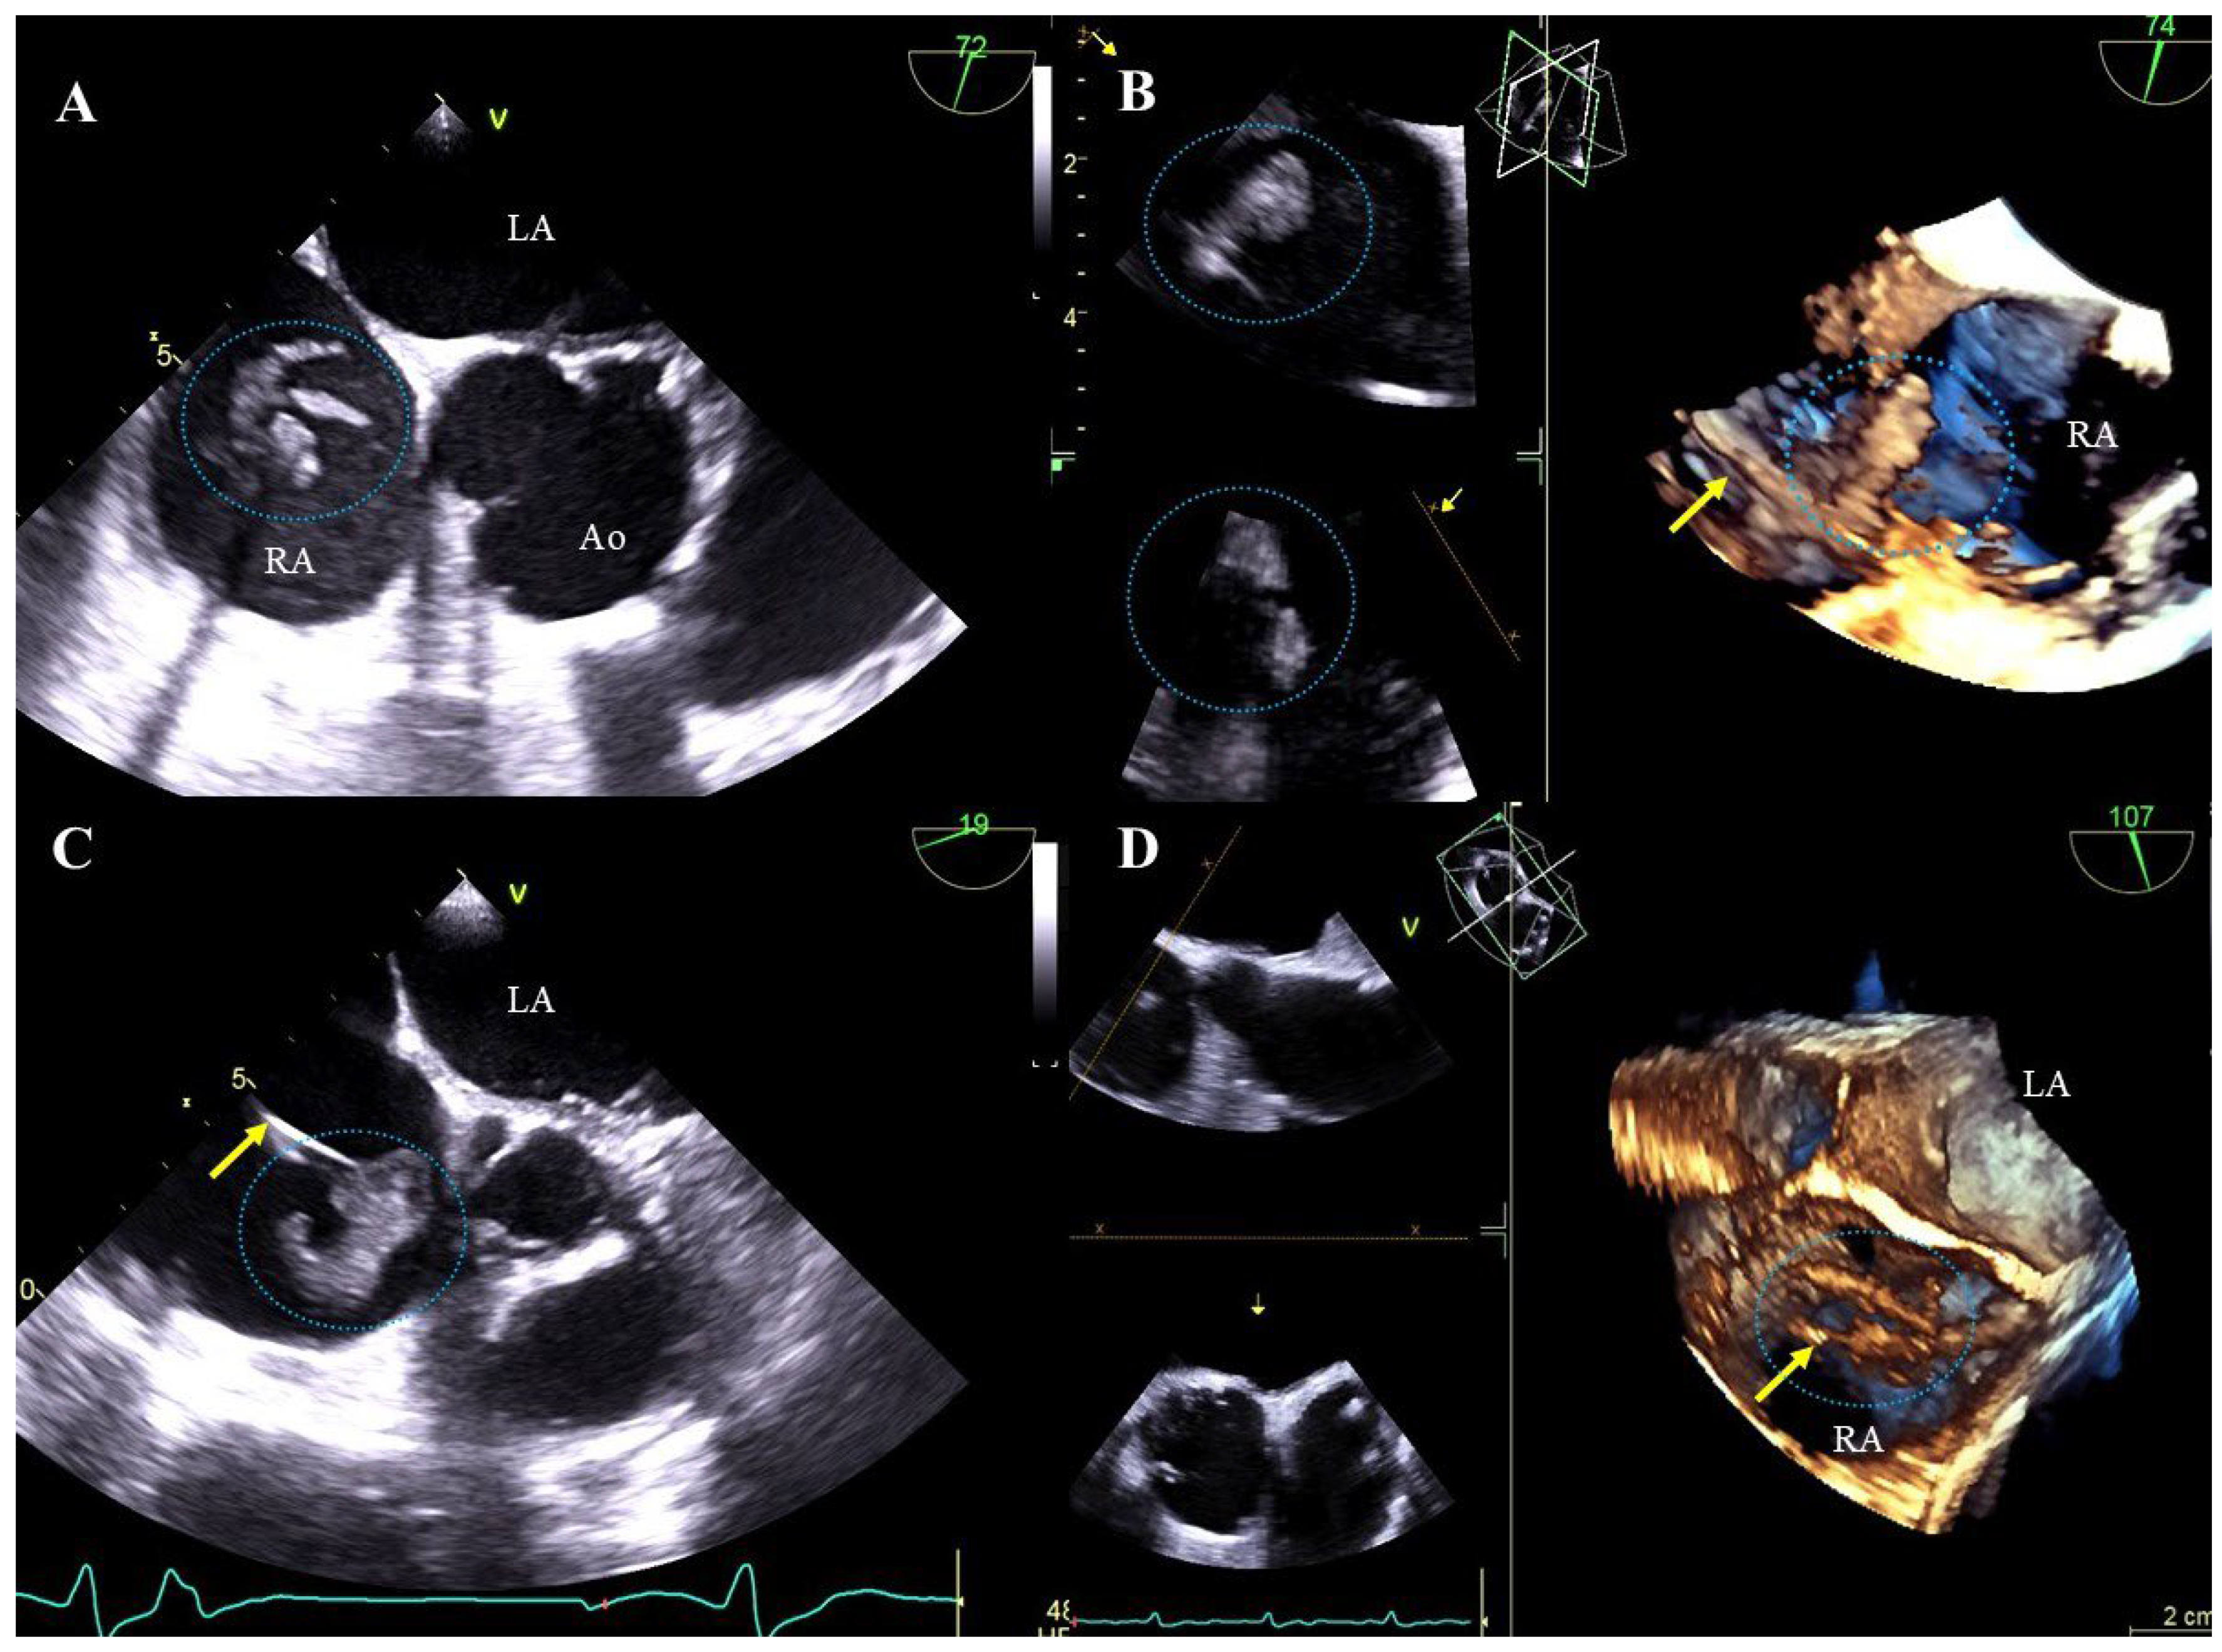

Floating scar tissue attached to the lead: small, hyperechoic structures with uneven contours, more rigid and less mobile than clots of uniform echogenicity being components of scar tissue developed in response to lead presence. They probably arise from progressive fibrosis of non-lysed blood clots (Figure 1A, Movie S1).

Blood clots on the leads: most often airy, hypoechoic, flaccid, flag-like formations, sometimes large and hyperechoic with a smooth surface (Figure 1B, Movie S2).

Vegetation-like masses: well-saturated formations resembling vegetations in shape and mobility, associated with leads and recorded in patients without symptoms of infection. They are probably a residue of past infections (old fibrosed vegetations). It cannot be ruled out that these masses are unusual-looking old clots or adhesions (Figure 1C,D, Movie S3).

Figure 1. TEE (2D, 3D) before TLE showing additional structures on the leads. Mobile structures correspond to scar tissue on the atrial lead (dashed line) (A). The mass on the lead corresponds to a large thrombus visualized in the right atrium (B). In the right atrium, in the patient with no signs of infection, an additional structure on the lead was visualized, which may correspond to a veg-like structure (C). In the right atrium, in the patient with no signs of infection, an additional structure was binding two leads; this may represent scar tissue or a veg-like structure (D). (Yellow arrows mark the electrodes, and additional structures are displayed in circles.).